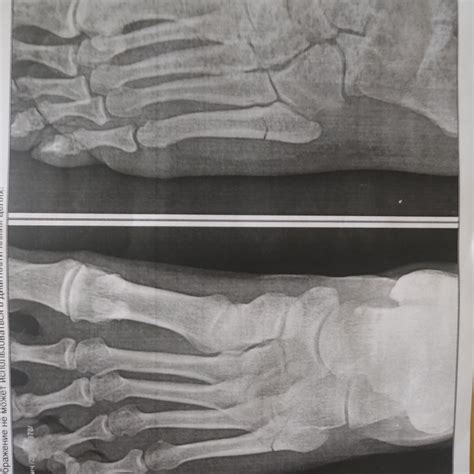

Динамика сращения перелома пятой плюсневой кост...

Косой перелом 5 плюсневой кости - Вопрос ортопе...

Перелом 5-ой плюсневой кости - Вопрос ортопеду-...

Перелом 5 плюсневой кости со смещением - Вопрос...